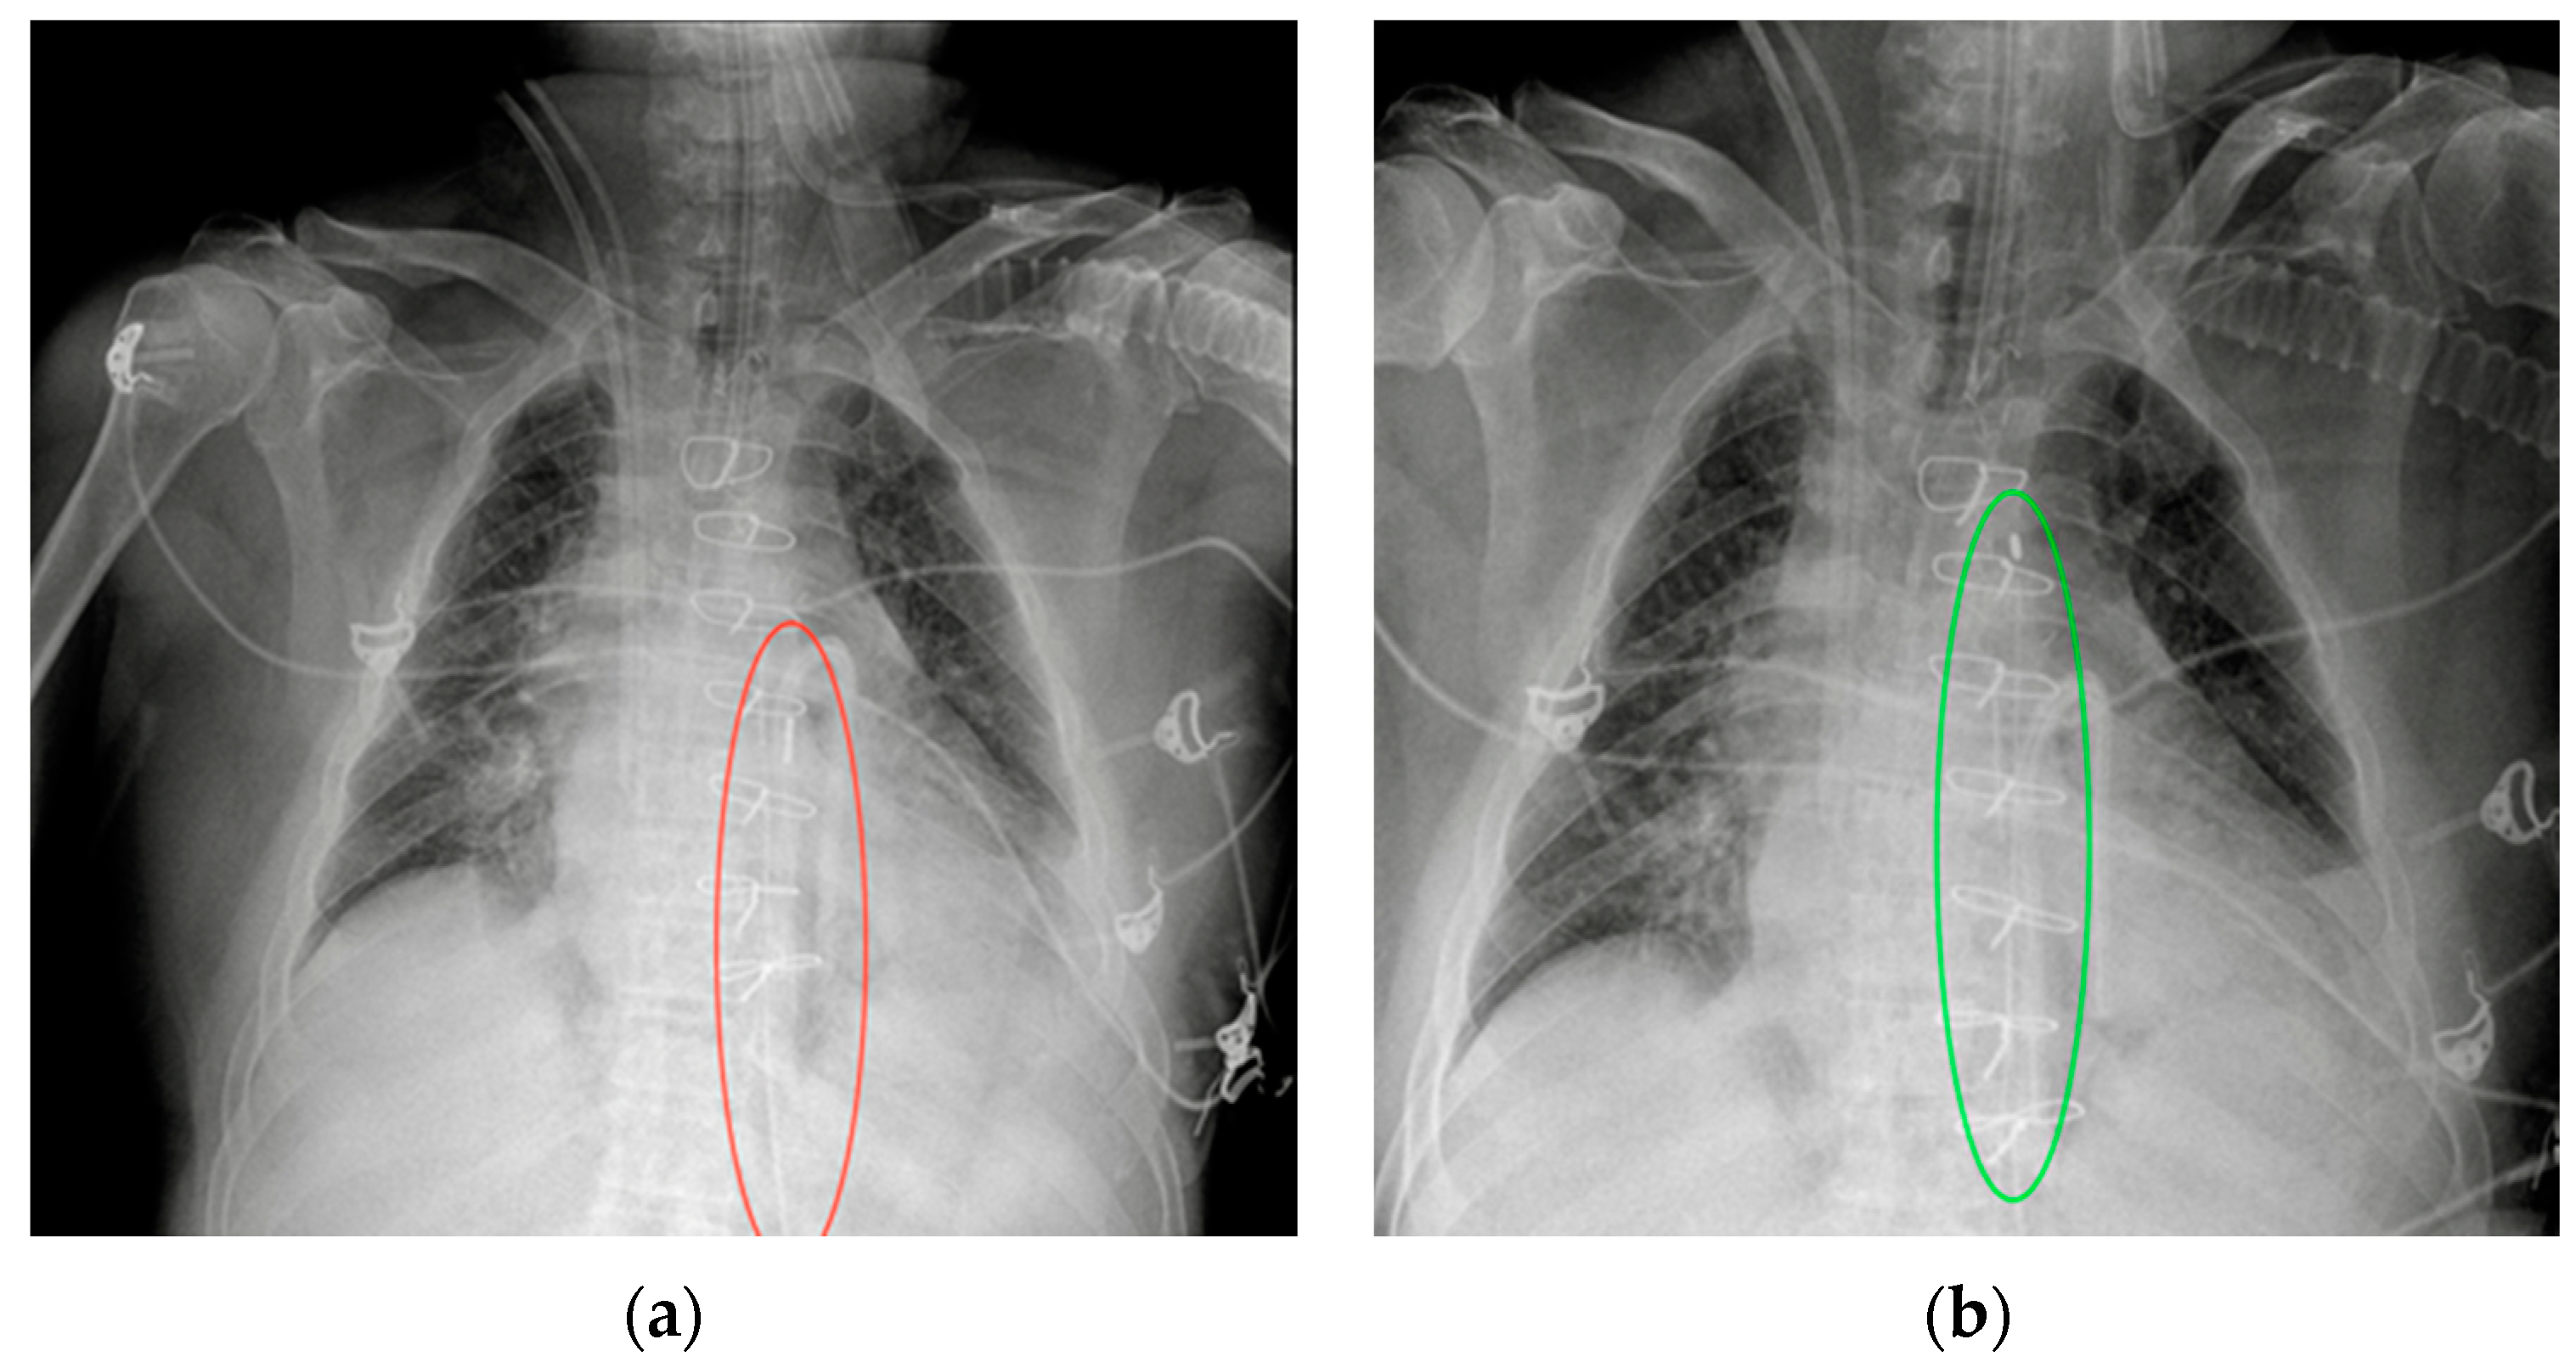

Figure 17.

Malpositioned IABP. (a) Anteroposterior CXR of a patient with an IAPB placed too distal from the aortic arch: the upper radiopaque mark can be seen at the level of the sixth intercostal space (red circle). (b) The same patient after repositioning of the IABP, with the upper mark now just under the aortic arch, in the proximal thoracic descending aorta, at the level of the fourth intercostal space (green circle).